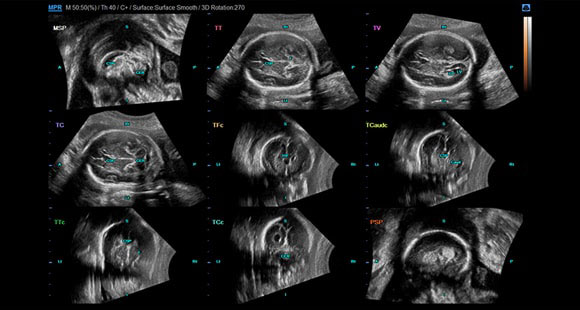

5D CNS

5D CNS vă permite să efectuați 6 măsurători

(diametrul biparietal BPD, circumferința capului HC, diametrul occipito-frontal OFD, grosimea atriului ventriculilor laterali Vp, diametrul cerebelos transversal TCD, dimensiunile cisternei magna CM) pe 3 planuri transversale ale creierului fetal, care sunt indicatori fundamentali pentru vizualizarea intuitivă a creierului fătului. Două clicuri simple vă permit să accelerați examinarea și să creșteți numărul de pacienți examinați.